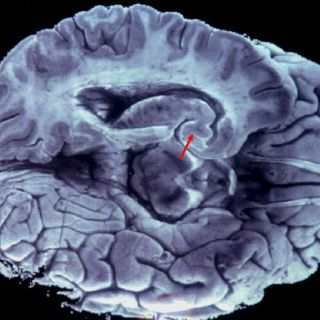

Millones de fibras conectan una mitad y otra del cerebro de mamíferos, que juntas forman el cuerpo calloso y transmiten información esencial para que los dos hemisferios cerebrales puedan comunicarse entre sí, señala el CNB en una nota.